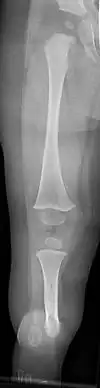

| a, b) Paley type 3c fibular hemimelia | |

Fibular hemimelia or longitudinal fibular deficiency is "the congenital absence of the fibula and it is the most common congenital absence of long bone of the extremities."[1][2] It is the shortening of the fibula at birth, or the complete lack thereof. Fibular hemimelia often causes severe knee instability due to deficiencies of the ligaments. Severe forms of fibula hemimelia can result in a malformed ankle with limited motion and stability. Fusion or absence of two or more toes are also common.[3] In humans, the disorder can be noted by ultrasound in utero to prepare for amputation after birth or complex bone lengthening surgery. The amputation usually takes place at six months with removal of portions of the legs to prepare them for prosthetic use. The other treatments, which include repeated corrective osteotomies and leg-lengthening surgery (Ilizarov apparatus), are costly and associated with residual deformity.[4]

- Absence of the lateral part of the ankle joint (due to absence of the distal end of the fibula), and what is left is unstable; the foot has an equinovalgus deformity